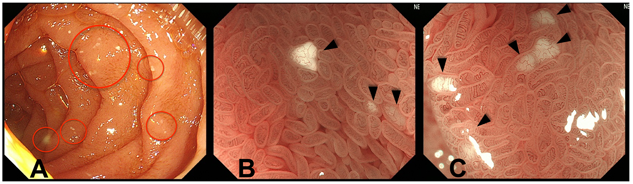

A 34-year-old female complained of diarrhea possibly due to PLE, as her mean right atrial pressure was 19 mmHg. She was born with tricuspid atresia and pulmonary atresia, and underwent the APC Fontan operation when she was 9 years old. She had suffered from severe hypo-albuminemia since she was 20 years old, and had a serum albumin level of approximately 1.2–1.4 mg/dL. Albumin scintigraphy revealed intestinal albumin loss including descending portion of duodenum (Fig. 1). Gastroduodenal endoscopy was performed to elucidate the causes of the albumin loss, during which edematous intestinal mucosa and duodenal villi were observed. Many villi were white, which was presumably related to enlargement of the lymphatic vessels (Fig. 2 A–C).

Fig. 1 Albumin scintigraphy

Albumin scintigraphy revealed albumin loss from the duodenum and jejunum even in early phase.